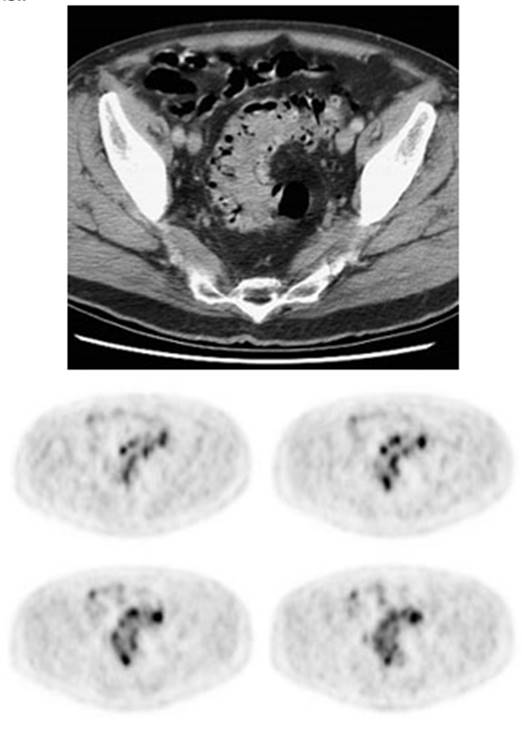

Figure 16 - Focal colonic uptake

associated with colon cancer: This patient had focal tracer uptake in the region of the cecum. CT

demonstrated a soft tissue mass which was found to be a primary colon cancer on

colonoscopy. Focal areas of colonic tracer uptake should be further evaluated.